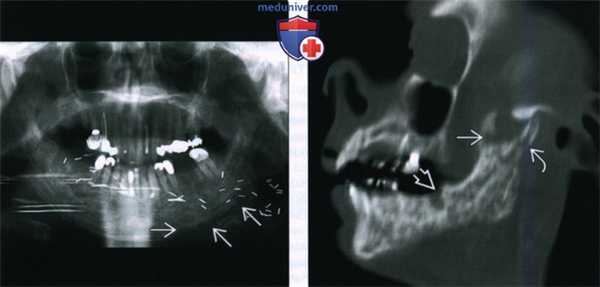

(Слева) На ортопантограмме у пациента, которому было выполнено оперативное вмешательство в сочетании с облучением полости рта, определяется диффузное утолщение и склероз нижней челюсти, утолщение трабекул и отсутствие дифференцировки кортикальной пластинки в области нижнего края нижней челюсти слева.

(Справа) При сагиттальной (под углом) реконструкции определяется, что нижняя челюсть имеет неоднородную структуру за счет множественных очаговых просветлений; определяется нарушение целостности кортикальной пластинки, утолщение и склероз трабекул и кортикальной пластинки. Обратите внимание на глубокий дефект, оставшийся после удаления моляра. Шейка мыщелка нижней челюсти и венечный отросток фрагментированы.

(Слева) На панорамной дентальной рентгенограмме у пациента, которому ранее было выполнено оперативное вмешательство и осуществлялась лучевая терапия полости рта, определяется диффузное утолщение и остеосклероз нижней челюсти, утолщение и деформация трабекул, нарушение дифференцировки кортикальной пластинки в области нижнего края нижней челюсти слева.

(Справа) При сагиттальной КТ (по углом) определяются множественные неоднородные «просветления» в кости, нарушение целостности кортикального слоя, утолщение и склероз трабекул и кортикальной пластинки. Обратите внимание на глубокую «лунку», оставшуюся после экстракции моляра. Определяется также фрагментация венечного отростка и шейки мыщелка.